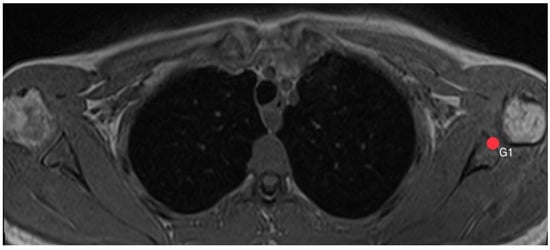

2.3. Acromion Index (Figure 1)